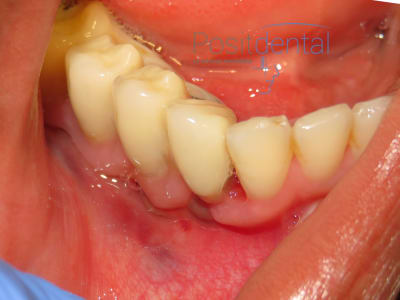

patiente en fin d'intervention

> patiente en fin d'intervention

bien de laisser le lambeau libre en regard de 42... j'espere que c'est une blague.

sinon bien le lambeau libre qui flotte en fin d'intervention... un florilege :)

bin au moins suturer les lambeaux... un minimum quoi...

mais serieusement, la c'était vraiment fini ? elle est allée en salle de réveil comme ca ?? :

donc elle est bien allee en salle de reveil non suturee... vache...

la sincèrement c est quand meme pas terrible... je veux bien rigoler un peu mais ca c est pas acceptable.